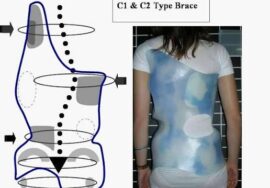

الحزام (أو الدعامة الطبية) يُعد من أهم الوسائل غير الجراحية لتصحيح أو تثبيت الانحناء، لكن فعاليته تعتمد على الالتزام بالمدة المحددة يوميًا.

بعض المرضى يخطئون بعدم ارتداء الحزام إلا لبضع ساعات، أو يخلعونه أثناء النوم أو المدرسة، مما يقلل فعاليته.

التزمي بتعليمات الطبيب حول عدد ساعات ارتداء الحزام (غالبًا بين 18 إلى 23 ساعة يوميًا).

احرصي على متابعة بشرة الطفل لتجنب الاحمرار أو التهيج، مع تنظيف الحزام بانتظام.

أحدث التقنيات العالمية: نعتمد على تقنيات حديثة مثل أجهزة التقييم الدقيقة وأحزمة التقويم المتقدمة مثل PioBrace.